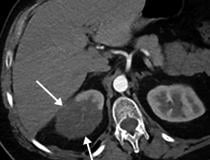

This photo gallery shows the variety of radiological presentations of COVID-19 (SARS-CoV-2) in medical imaging, including computed tomography (CT), radiograph X-rays, ultrasound, echocardiograms and magnetic resonance imaging (MRI). The radiology images show examples of typical COVID pneumonia in the lungs and the numerous complications the virus causes in the body in multiple organs, including the brain, kidneys, heart, abdomen and vascular system.